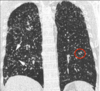

19

Q

A

Patrón intersticial reticular

How well did you know this?

1

Not at all

2

3

4

5

Perfectly